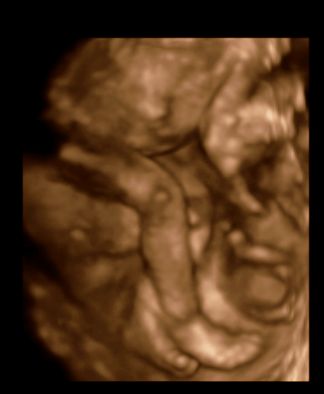

Nagyon szépek a Dalma fotók! :) :) :) ahol látszik a kis combja, ott tényleg olyan husika! :) :) :)

Van egy combos lábas kép is.

Kép